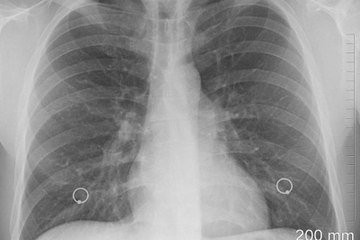

#ممكن | د.حسام عبدالغفار : وفاة 4 أطفال بسبب الإلتهاب الرئوي